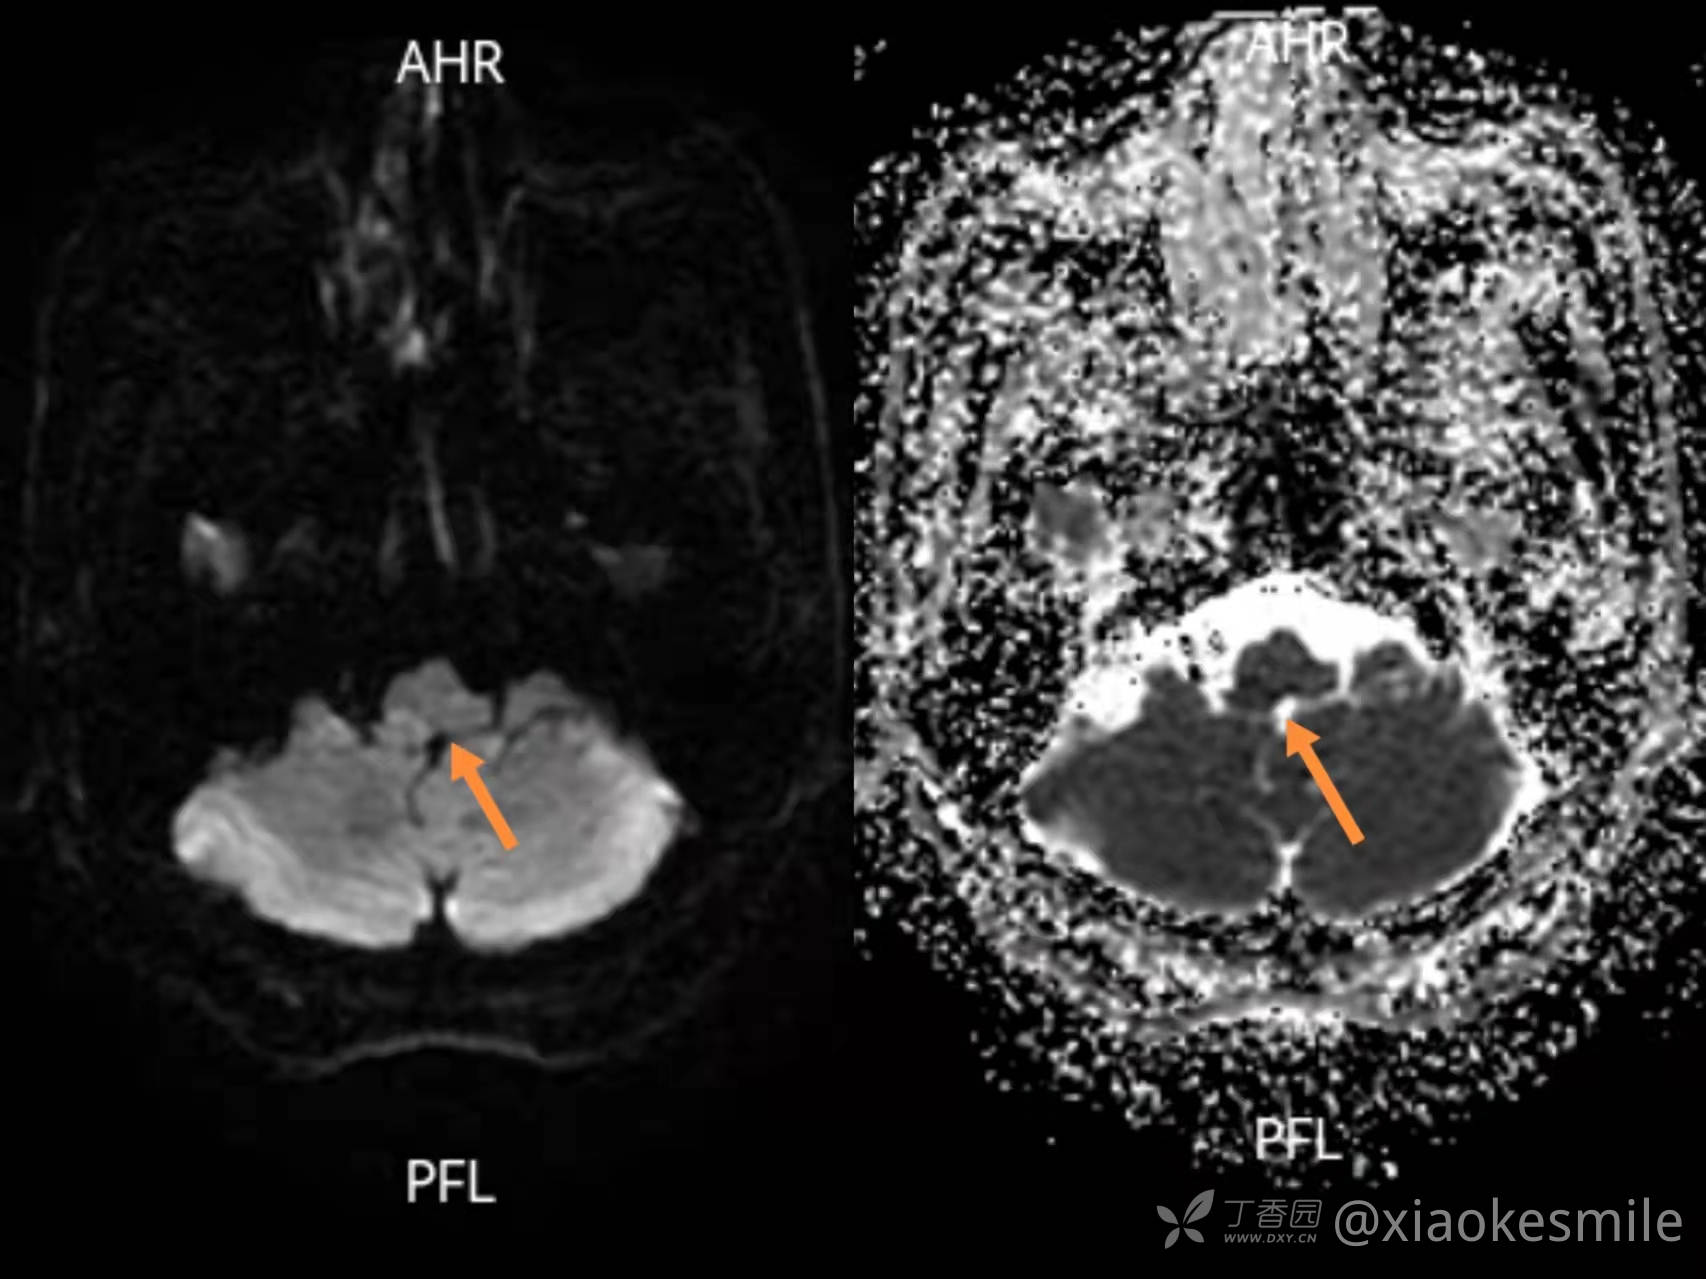

入院后完善相关化验检查提示延髓梗死(图1)。

图一 左图可见右侧延髓DWI高信号,右图ADC低信号(患者发病<12小时,此为脑干+小脑薄扫核磁共振)入院后完善其他相关化验检查,头颈部CTA检查未见异常。脑血管病相关危险因素筛查,除患者吸烟饮酒外,还有高血压、高脂血症、高同型半胱氨酸血症。入院后给予抗血小板聚集、调脂稳定斑块、改善循环、脑保护及补液扩容等治疗,患者病情逐渐好转,头痛也较前明显减轻。